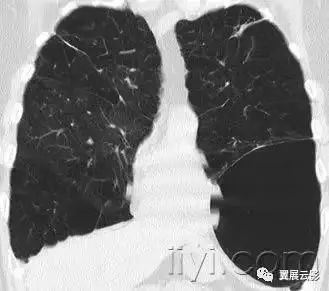

小叶中心性异常包括(1)结节(2)树芽征,提示小气道病变(3)由于临近间质的增厚或者浸润导致小叶中心结果更加清晰(4)小叶中心性肺气肿导致的异常低密度。

附图为小叶中心性肺气肿